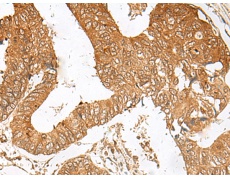

IHC positive control:

Human cervical cancer and Human thyroid cancer

IHC Recommend dilution:

50-300